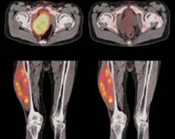

Pruebas de imágen

Las pruebas de diagnóstico por imágenes utilizan ondas sonoras, rayos X, campos magnéticos o sustancias radiactivas para crear imágenes del interior del cuerpo. Las pruebas de diagnóstico por imágenes pueden realizarse por diversos motivos, como:

Las imágenes más representativas o más comunes son:

1. Radiografías de tórax

2. Ultrasonido

3. Tomografía Computarizada

4. PET scan

5. Resonancia Magnética